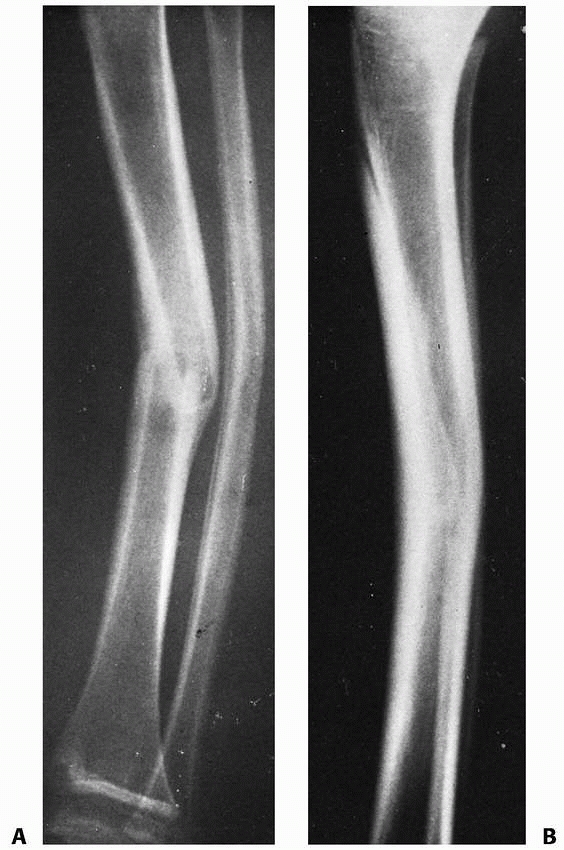

![]() |

FIGURE 25-33 A 50-month-old child with a middle one-third transverse tibial fracture and a plastically deformed fibular fracture. A. Lateral view shows 20-degree posterior angulation. B. The deformity is still 15 degrees 4 years after the injury.

|